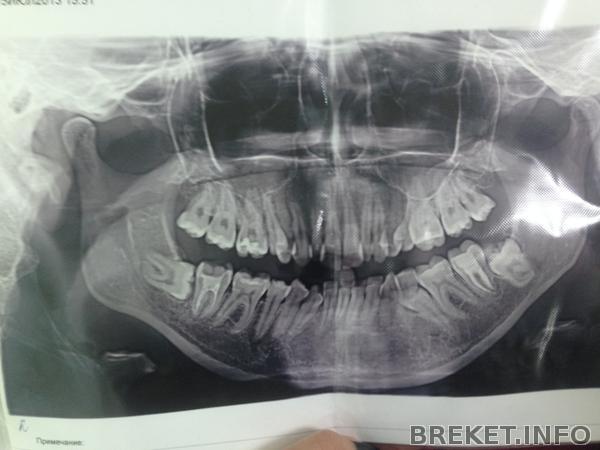

Ну и панорамный снимок.

На фото справа моя невылезсшая пятерка и восьмерка которую предлагает удалить орт.